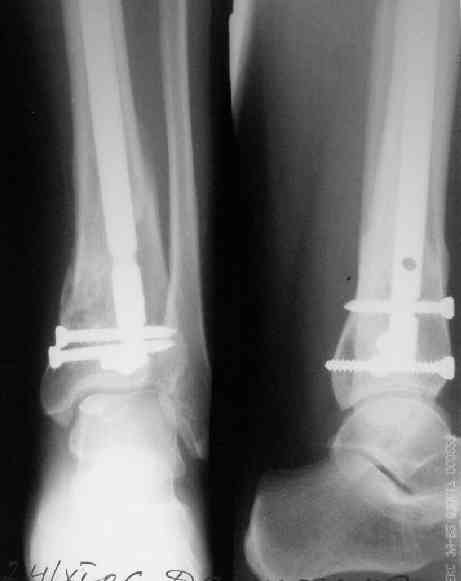

В приложении пример лечения аналогичного повреждения (плюс задний край).

Выполнил MIPO предизогнутой метафизарной LCP

Красиво получилось, поздравляю. Насчет немедленной полной нагрузки, как на гвозде, про что Алексей Семенистый говорит - будете разрешать сразу?

И все же немного критики:1) Вы добивались анатомичной репозиции, которая требует абсолютной стабильности, которая в свою очередь возможноа только в условиях межфрагментарной компрессии. Пластина уложена как мостовидная, не хватает стягивающнго винта. 2) есть укорочение малоберцовой кости, необхордимо восстановить ее длину! В таком виде я бы не стал разрешать раннюю нагрузку. Добавить самую малость: стягивающий винт и остеосинтез малоберцовой кости и больной может наступать сразу.

> есть укорочение малоберцовой кости, необхордимо восстановить ее длину